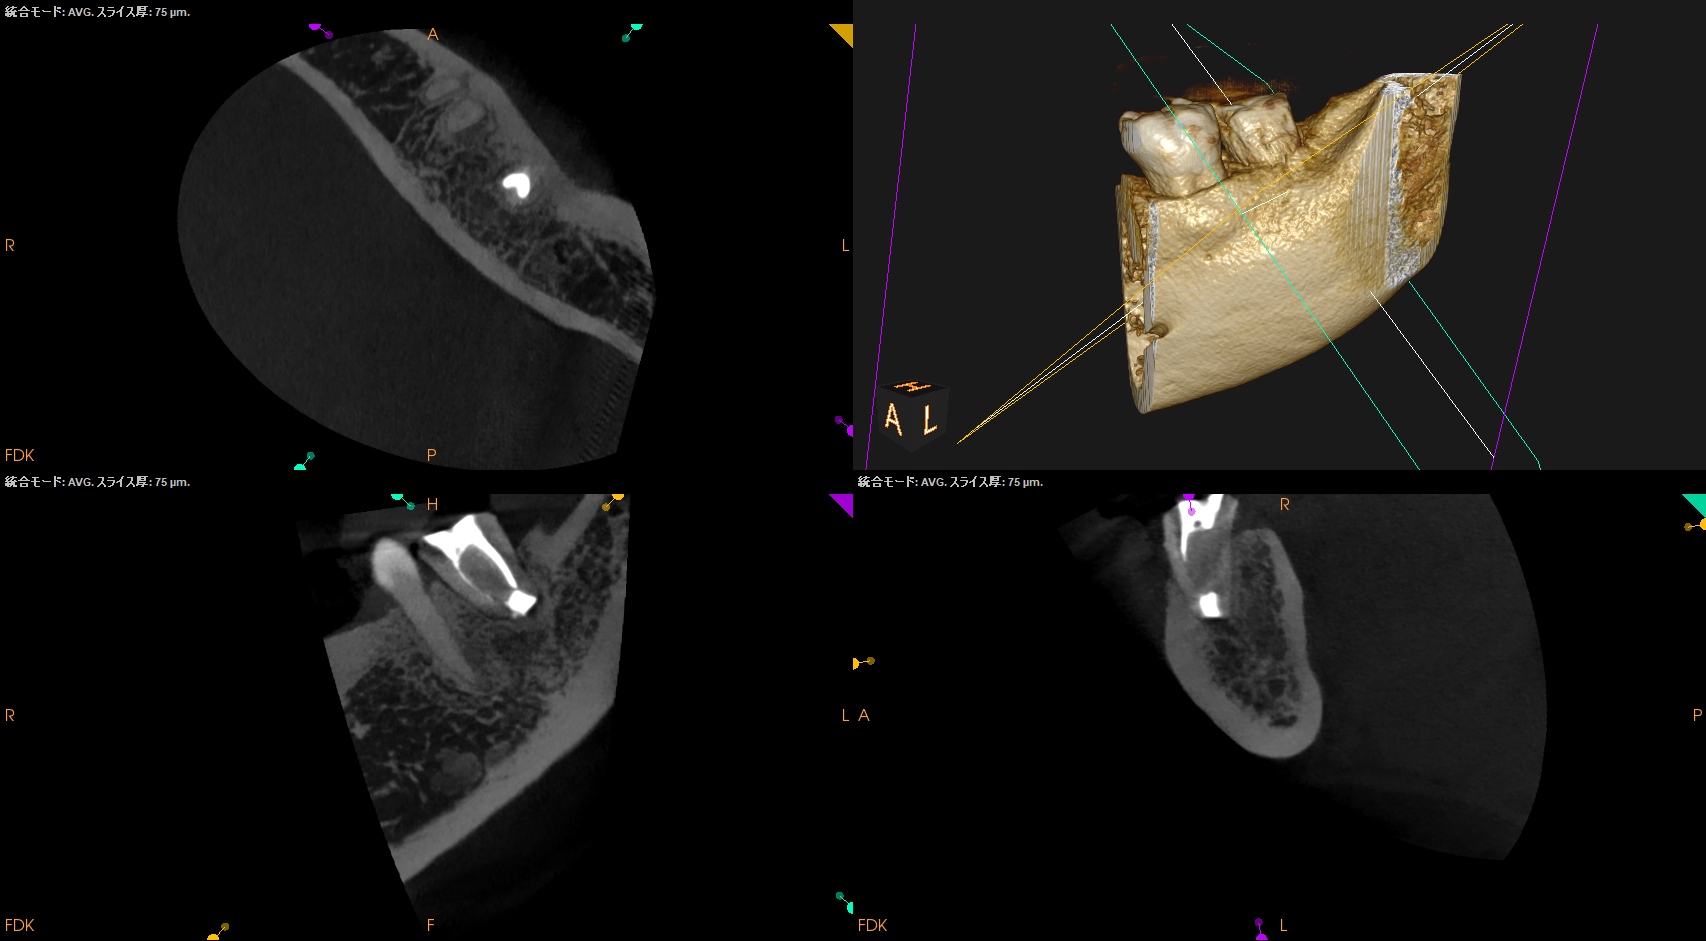

#18 Intentional Replantation 1.5yr recall(2025.11.25)

初診時にあった歯肉の腫脹(↓)は消失していた。

初診時と比較した。

5年前から悩まされていた歯肉の腫脹は消失し、歯槽骨も完治した。

打診検査時のアンキローシス音もないことからこの日で終診とさせていただいた。